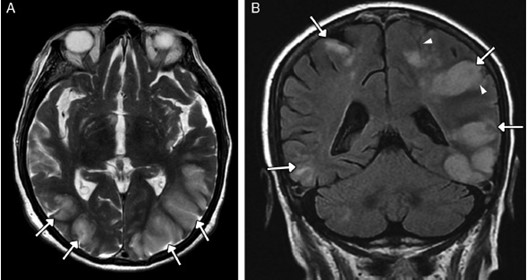

Se pueden mencionar al respecto los estudios que han encontrado en pacientes dependientes al alcohol una disminución del volumen de sustancia gris en el área de la corteza frontal, el hipocampo y el tálamo. El volumen de las sustancias blanca y gris también se puede ver disminuido en el área periventricular, la protuberancia y el cerebelo. Estos déficits de volumen también se han localizado en la corteza prefrontal dorsolateral derecha, ínsula anterior derecha, en el núcleo accumbens y en la amígdala izquierda(16) (ver Imagen 1).

Asimismo, como se indicó previamente, a través de la TC también se puede observar el deterioro de la microestructura cerebral por adicción al alcohol. El abuso de esta sustancia altera cinco fibras del cerebro, como el cuerpo calloso, el fondo de saco, la cápsula externa, el cíngulo circunvolución y el fascículo longitudinal superior, las que están involucradas en funciones como el procesamiento visoespacial y del lenguaje, la comunicación interhemisférica, la memoria, el procesamiento emocional, la toma de decisiones y la integración sensorial(16) (ver Imagen 2).